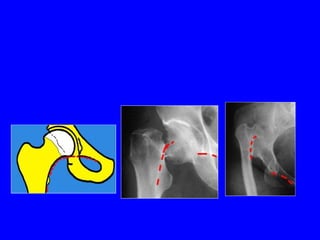

Coxa Valga e Displasia del cotile

Coxartrosi su coxa valga e displasia dei cotili

Coxa Valga eDisplasia del cotile

Coxartrosi su coxavalga e displasia dei cotili